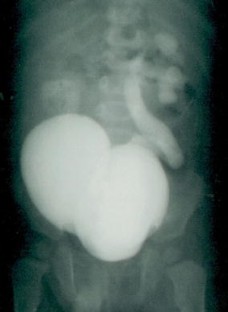

All were males. Age at presentation ranged from six months to eight years (mean three years). All were diagnosed postnatally by ultrasound and/or voiding cystourethrography (VCUG) and confirmed on urethrocystoscopy. Open surgical excision of diverticulum was done in all the patients. Ureteral reimplantation was simultaneously done only in three patients with VCUG-documented high-grade vesicoureteral reflux (VUR). With an average follow-up of four years, gradual resolution of symptoms was seen in seven of nine patients whose postoperative follow up records were available. There was no diverticulum recurrence at the defined mean follow-up.

Pediatric patients with recurrent urinary tract infections and voiding dysfunction should always be evaluated for congenital bladder diverticulum. Although investigations such as intravenous urography (IVU), urodynamic studies, nuclear renal scanning, and, sometimes, CT scan and MRI, form an important part of preoperative diagnostic work-up and postoperative follow up, USG and VCUG may be enough when availability and cost are the constraints. Diverticulectomy, with ureteral reimplantation for high-grade reflux, provides good results without recurrence.

Fig. 2